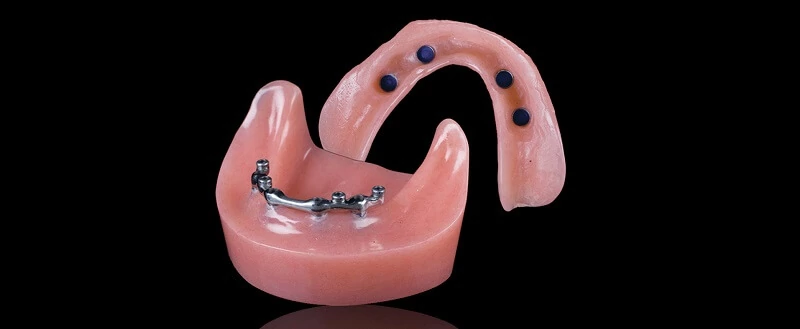

Пошаговое руководство по установке съёмного протеза на импланты